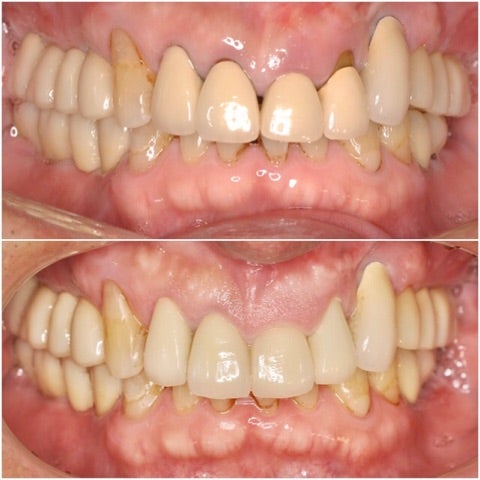

初診時

▶︎実際両側の奥歯には計10本以上のインプラントが埋入されています。

after

▶︎手術の傷口もほとんどわからない程度まで回復しています。(写真右上前歯部分)

before/after

歯の動揺がなくなったことはもちろん、歯と歯茎の黒い境目や、形態不良による審美障害も改善されています。ご本人には自分の歯が残せたこと、見た目も綺麗になったことでとても喜んで頂けました。